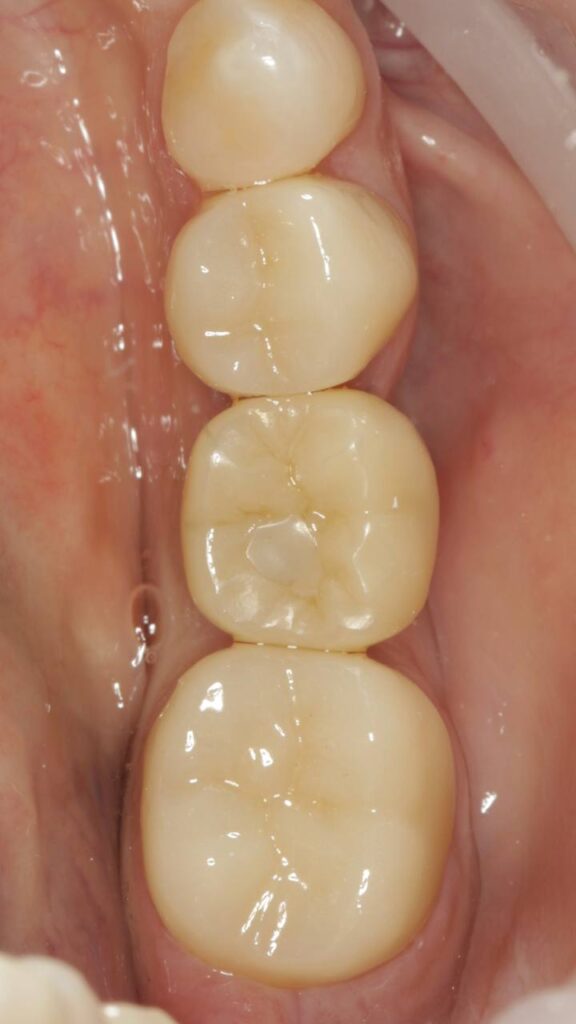

Протезирование коронками из диоксида циркония, после эндодонтического лечения — Исламов Л.А.(01.04.2026)